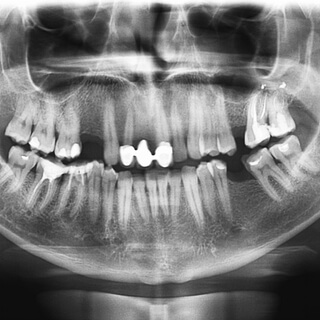

1. تصوير السن المراد صنع تلبيسة له باستخدام الصور الإشعاعية.